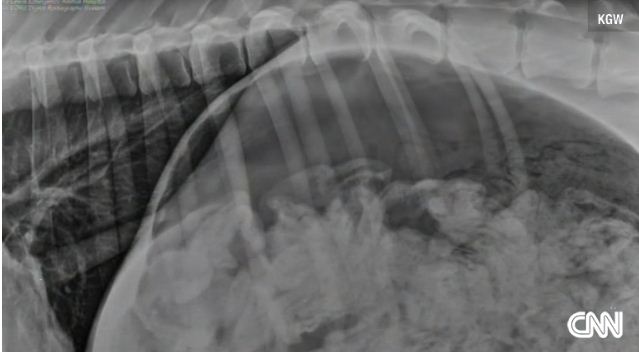

Η ακτινογραφία που δόθηκε στη δημοσιότητα είναι χαρακτηριστική, όπως επίσης και η φωτογραφία των... «διασωθέντων» καλτσών από το στομάχι του σκύλου.

Γιατί αυτό; Γιατί οι γιατροί χρειάστηκε με επίπονη και πολύωρη επέμβαση να αφαιρέσουν από το στομάχι του σκύλου, όχι μία και δύο αλλά 43 ολόκληρες κάλτσες, «σαν καινούριες» που λέμε, και μία... μισή!

«Ανοίξαμε το στομάχι του και βγάζαμε τις κάλτσες μία - μία, σε κάθε χρώμα και μέγεθος» λέει στο CNN o δρ. Μάγκι από το Όρεγκον των ΗΠΑ που έκανε το χειρουργείο.